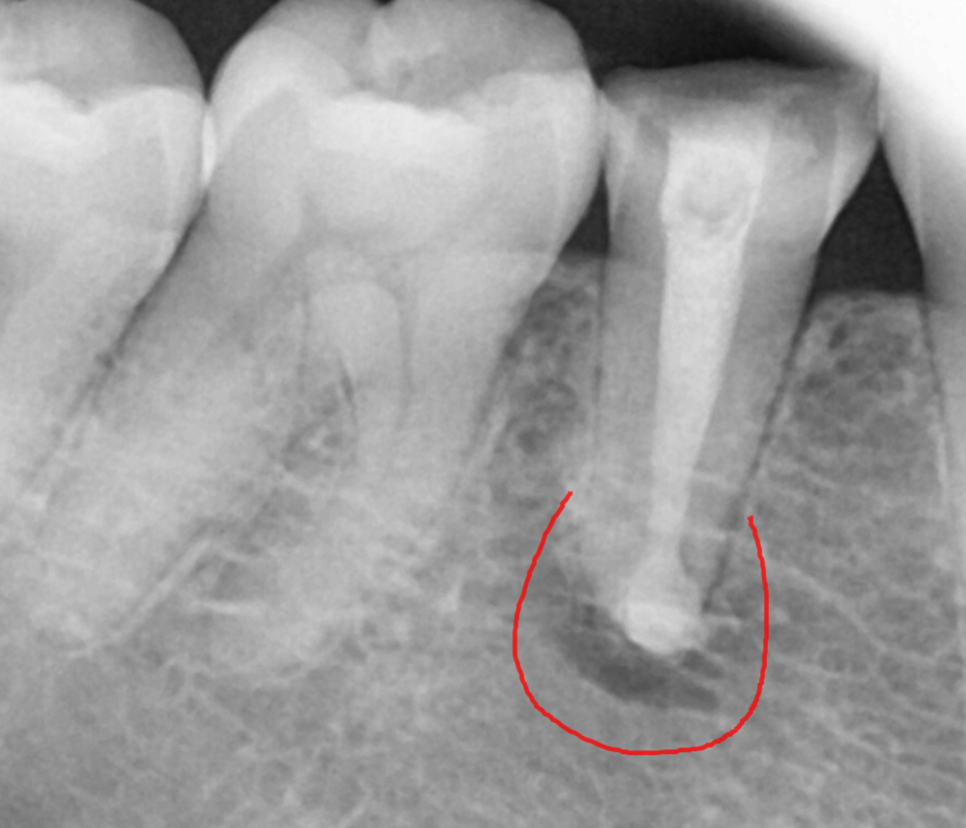

240312 뿌리 끝 염증

오늘 환자분처럼 신경치료 후 보철을 씌워주지 않으면

치아가 약해지면서

다양한 문제가 생길 수 있어요.

241026

속부터 건강하게 원인을 파악하면

치료해주면